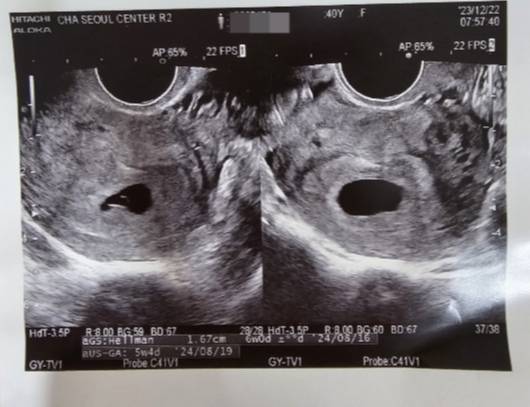

그렇게 기다리고 기다리던 아기가 찾아왔어요. 5주4일 첫 초음파 사진을 봤어요. 얼마나 예쁘게 아기집을 지어놨는지 벌써 대견합니다.

벌써 입덧이 시작되고, 몸이 힘들지만, 아기가 잘 있다고 하는 것 같아 뭉클합니다.

사실은 아직 너무 초기라 소문내지도 못했습니다. 하지만 많은 분들께 축복받으면 아이가 더 건강해질 것 같아 자랑해 봅니다. 그리고 10년 동안 저와 잘 살아준 신랑에게도 고맙습니다.

하트야, 8월에 건강하게 만나자. 엄마가 잘해줄게!